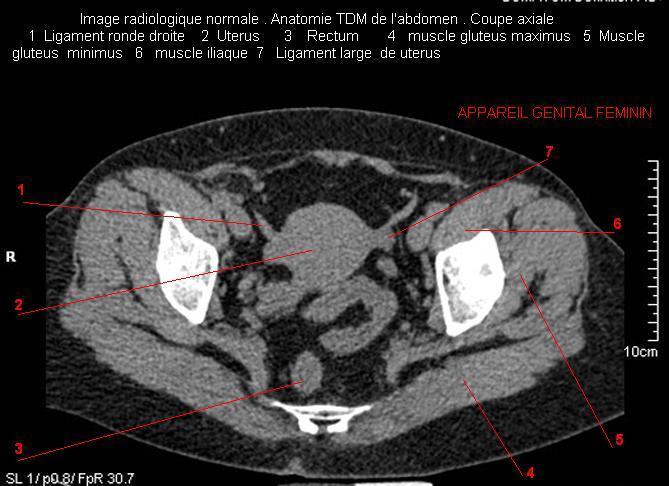

Image radiologique TDM normale de l'abdomen et tube digestif en coupe axiale ( CT scanner )  :

Coupe axiale     Coupe frontale      Coupe  sagitale